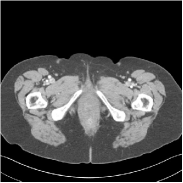

Fig. 2 shows a test example reconstructed using various methods.

Refer to caption

Figure 2: Reconstructions of slice 100 from patient L192 using various methods. The display window is [800 1200] HU.

We observe that PWLS-EP reduces the severe noise and streak artifacts observed in the low-dose FBP images, and the transform learning-based method PWLS-ULTRA further suppresses noise and reconstructs more details of the image such as the zoom-in areas. However, both methods have some blurry artifacts. The standalone FBPConvNet method heavily removes noise and streak artifacts, while introducing several artificial features (e.g., feature indicated by the arrow in the top-right box in Fig. 2). WavResNet denoises the image without introducing artifical features, but still retains some streaks around image boundaries and blurs some details (e.g., feature indicated by the arrow in the bottom-left box in Fig. 2). The state-of-the-art MAP-NN method performs slightly better than WavResNet in terms of suppressing streak artifacts, while it still loses some details as indicated in the zoomed regions. The competing plug-and-play unrolled method—ADMM-Net with WavResNet denoiser—outperforms the standalone WavResNet method, but still has some streak artifacts and blurred details. Compared to these methods, the proposed SUPER methods (SUPER-WRN-EP, SUPER-WRN-ULTRA, SUPER-FCN-EP, and SUPER-FCN-ULTRA) improve the reconstruction quality in terms of removing noise and artifacts, and recovering details more precisely. Two other example comparisons are included in the supplement (Fig. 10 and Fig. 11).